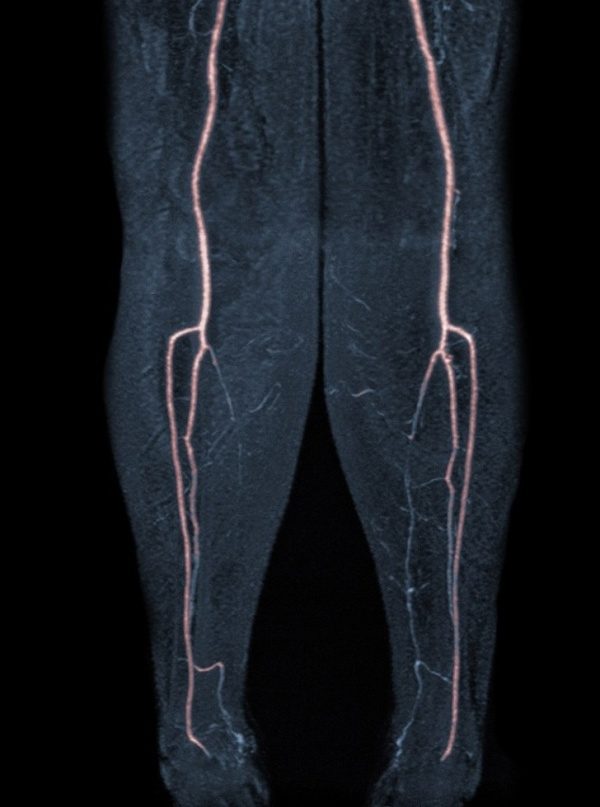

На левой ноге можно увидеть, как выглядит закупорка сосудов